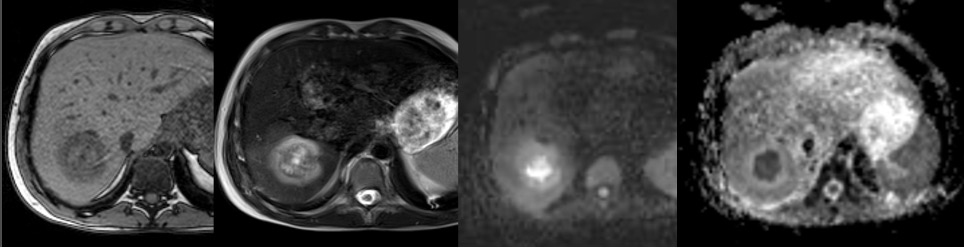

Aspetto RM

- Alterazione focale caratterizzata da segnale intermedio in T2, isointensità in T1, con abbattimento del segnale nelle sequenze in opposizione di fase per la presenza di grasso intralesionale.

- Allo studio dinamico si caratterizza per precoce enhancement arterioso con isointensità tardiva.

- In fase epatospecifica è ipointenso rispetto al parenchima circostante per l’assenza di un sistema duttale biliare

Aspetto RM

- Alterazione focale disomogeamente ipointensa in T1, iperintensa in T2, con sfumato alone periferico dato dall’edema perilesionale, caratterizzata da enhancement periferico e ipointensità in fase epatospecifica.

- DWI/ADC: restrizione centrale – componente corpuscolata.